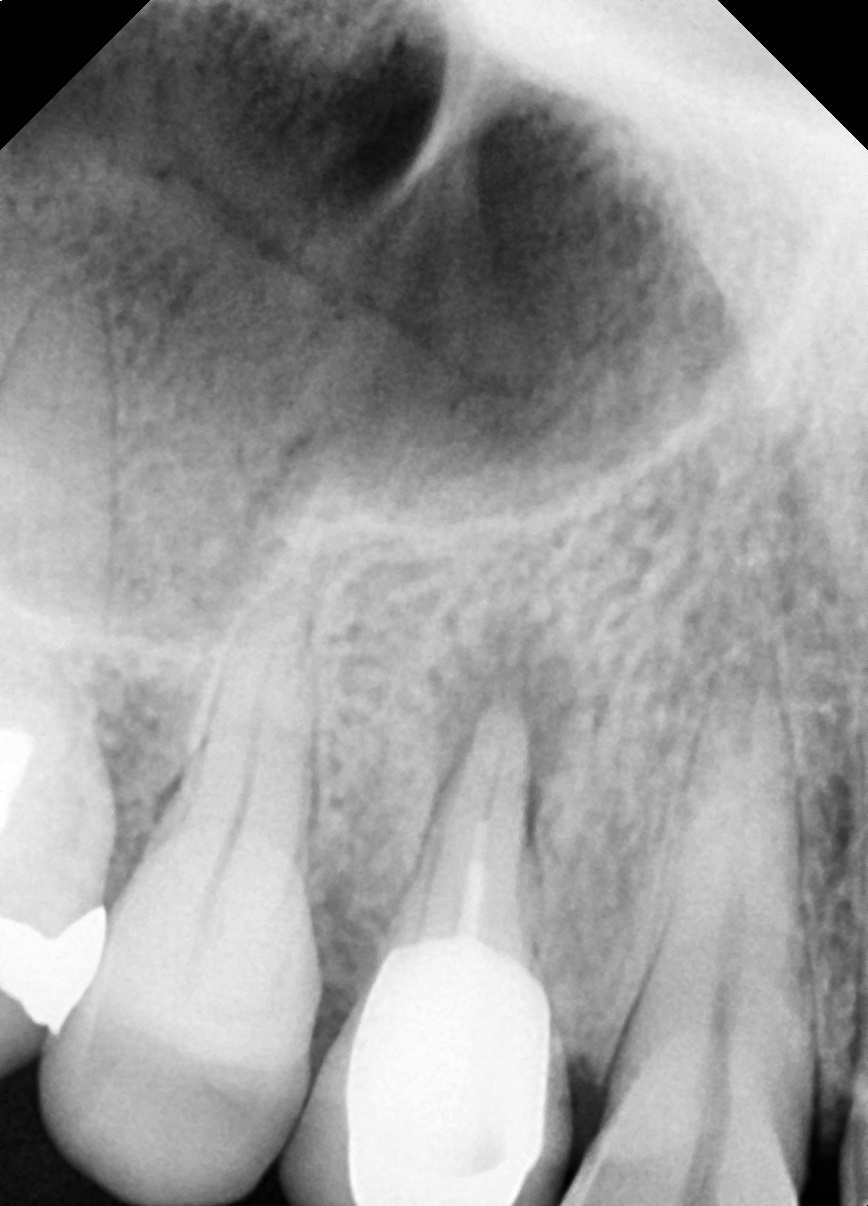

재신경치료

다른 병원 치료 후 재발한 어금니

Before

After

재신경치료로 추가 근관을 찾아 1년 9개월 후 완치